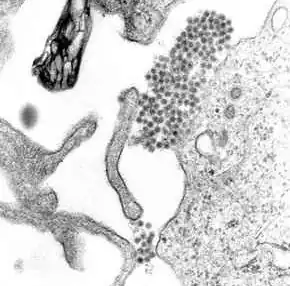

Das Denguefieber [], auch Dandyfieber, Polkafieber, Knochenbrecherfieber,[1] Siebentagefieber[2] und kurz Dengue ist eine Krankheit, deren Ursache eine Infektion mit dem Dengue-Virus ist. Bei dem Virus handelt es sich um ein 40 bis 60 nm großes, behülltes RNA-Virus mit positiver Polarität aus der Familie der Flaviviren.

Denguefieber wird durch einen der vier Serotypen (DENV-1 bis DENV-4) des Dengue-Virus verursacht, es handelt sich um ein rundes behülltes Virus mit einem Durchmesser von 40 bis 60 nm aus der Familie der Flaviviren. Das virale Genom besteht (im Gegensatz zu der von allen Lebewesen verwendeten DNA) aus Ribonukleinsäure (RNA). Das Genom ist etwa 11.000 Nukleotide lang und ist positivsträngig, kann also von Ribosomen direkt abgelesen und mit dessen Information ein Protein (Aminosäurenkette) gebildet werden. Das Genom umfasst nur einen offenen Leserahmen, der für ein Polyprotein codiert (eine lange Aminosäurekette, die nachher noch in die einzelnen funktionalen Proteine geschnitten werden muss).[6]

Während einer Infektion heften sich die Viren über spezifische Rezeptoren an der Zelloberfläche einer Wirtszelle an und werden durch ein sich ausbildendes Endosomvesikel aufgenommen. Normalerweise dienen diese Vesikel dazu, Stoffe zu verdauen, das Virus nutzt sie aber als Transportmöglichkeit, um ins Innere der Zelle zu gelangen. Im Innern des Endosoms induziert der saure pH-Wert die Fusion von Endosommembran und Virushülle, was dem Virus-Inhalt erlaubt, ins Zytosol einzudringen. Danach wird das virale Genom im rauen Endoplasmatischen Retikulum (ER) und in so genannten vesicle packets repliziert, und nach einer Reifung im Golgi-Apparat entstehen infektiöse Viruspartikel. Diese verlassen die Zelle und befallen weitere Wirtszellen.[6]